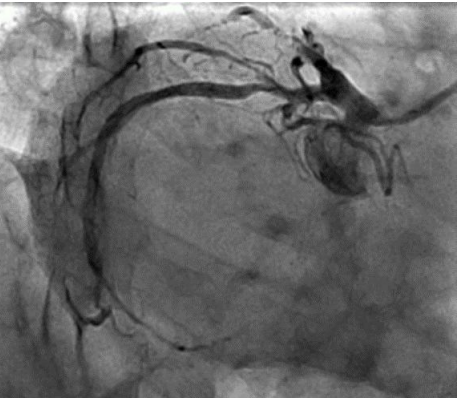

The patient then underwent elective coronary angiography which showed a Normal Left Main,  100% occluded Left Anterior Descending Artery, filling from right sided collaterals, a proximal 80% in the left circumflex with a 99% occluded OM1. The RCA had a proximal 80% lesion with a diffusely diseased acute marginal branch.

Figure 2 LAO Caudal View showing disease in the proximal LCX as wel disease in the proximal OM

Figure 3 RAO caudal view showing disease in the proximal and distal LCX as well in the proximal OM

Figure 4 LAO cranial view showi ng 100% occluded LAD

Figure 5 Tubular tight lesion prese nt in the RCA

Figure 6 The LAD being fed from collaterals from the RCA

Figure 2

Figure 3

Figure 4

Figure 5

Figure 6